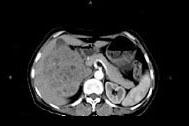

问题 女,57岁,右腰部胀痛6个月余,触及右侧腹部包块2个月,CT平扫及增强如图所示,下列说法正确的是 ( )

选项 A、考虑肿块来源于右肾,是巨大的肾癌,并挤压推移右肝,与其分界欠清 B、考虑肿块来源于右肾,是肾血管平滑肌脂肪瘤,并挤压推移右肝,与其分界欠清 C、增强扫描肿块强化明显,其内可见无强化的低密度坏死灶 D、考虑肿块来源于肝脏,是原发性肝癌,并挤压推移右肾 E、平扫时可见右侧腹部巨大的软组织肿块影,其内可见小片状的低密度影

答案 ACE